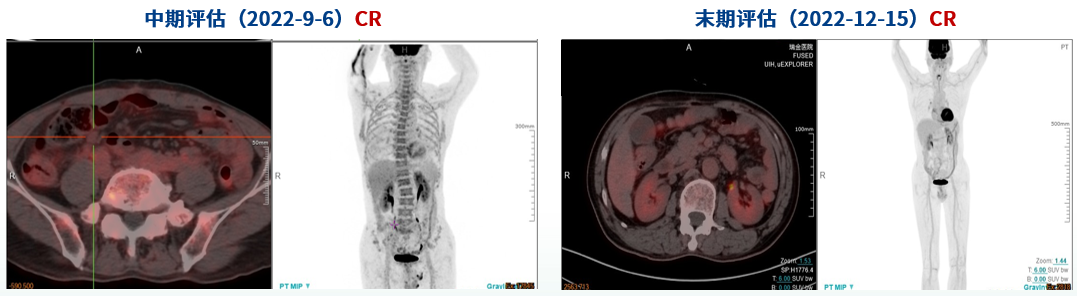

➤2022年9月6日和2022年12月15日的中期评估和末期评估中,患者的疗效评估为CR(图7)。

图7 中期评估和末期评估的PET-CT检查

本病例为初治男性DLBCL患者,PET-CT检查提示肿块代谢较高且左侧腋窝淋巴结出现肿瘤浸润。基因检测和免疫组化显示该患者伴C-MYC和BCL-6蛋白双表达,C-MYC和BCL-6重排。简化20基因算法分析显示该患者是MCD亚型。GUIDANCE-01研究提示BTK抑制剂联合R-CHOP可有效改善MCD亚型患者的缓解深度并延长生存2。因此,在R-CHOP治疗1个疗程并明确为MCD亚型后,给予奥布替尼联合R-CHOP治疗方案。本例患者在中期评估和末期评估时均获得CR,并在随访半年时仍为持续CR,验证了简化20基因算法分型准确及联合治疗方案起效迅速的特点。